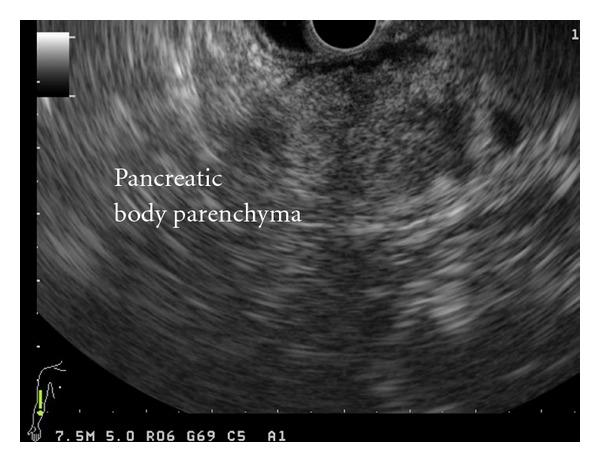

Bifid pancreatic duct represents a relatively rare anatomical variation of the pancreatic ductal system, in which the main pancreatic duct is bifurcated along its length. This paper describes the challenging surgical management of a 68-year-old male patient, with presumptive diagnosis of periampullary malignancy who underwent a successful double duct to mucosa pancreaticojejunostomy for bifid pancreatic duct. Following pylorus preserving pancreaticoduodenectomy, careful intraoperative inspection of the cut surface of the residual dorsal pancreas identified the main in addition to the secondary pancreatic duct orifice. Bifid duct anatomy was confirmed via intraoperative probing and direct visualization of the ductal orifices. A decision was made for the performance of an end-to-site double duct to mucosa pancreaticojejunostomy. Postoperative outcome was favorable without any complications. Although bifid pancreatic duct is relatively rare, pancreatic surgeons should be aware of this anatomical variation and be familiar with the surgical techniques for its successful management. Lack of knowledge and surgical expertise for dealing with this anatomical variant may lead to serious, life threatening postoperative complications following pancreatic resections.

胰管分支代表了胰管系统一种相对罕见的解剖变异,其中主胰管在其走行过程中发生分支。本文描述了一名68岁男性患者具有挑战性的手术治疗过程,该患者初步诊断为壶腹周围恶性肿瘤,因胰管分支成功接受了双管对黏膜胰管空肠吻合术。在保留幽门的胰十二指肠切除术后,术中仔细检查残留背侧胰腺的切面,除了二级胰管开口外还发现了主胰管开口。通过术中探查和直接观察导管开口证实了胰管分支的解剖结构。决定实施端对端双管对黏膜胰管空肠吻合术。术后结果良好,无任何并发症。尽管胰管分支相对罕见,但胰腺外科医生应了解这种解剖变异,并熟悉其成功治疗的手术技术。缺乏处理这种解剖变异的知识和手术专业技能可能导致胰腺切除术后出现严重的、危及生命的术后并发症。